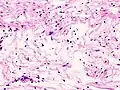

Micrograph of a schwannoma showing both a cellular Antoni A area (top) and a loose paucicellular Antoni B area (bottom). HE stain. | |

Verocay bodies are seen histologically in schwannomas.

Antoni A area of schwannoma with Verocay bodies (one annotated by circle)